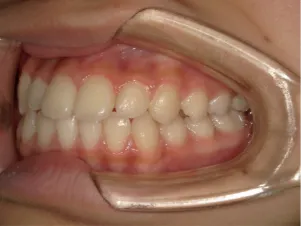

治療後⑩高2:17y7m 抜歯治療終了

口元の治療前後:15y5m→17y7m スッキリしました